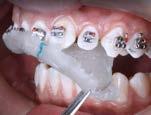

Figura 4. Imagen representativa de una férula flexible en la superficie labial del órgano dental afectado y en los dientes adyacentes. Tomada por el esp. Isidro Valdez Ramírez.

Un método de tratamiento para dientes traumatizados es la ferulización dental (Figura 4), que permite la curación del tejido periodontal y al mismo tiempo protege el diente de lesiones adicionales. La fijación flexible o semirrígida es suficiente para la curación pulpar y periodontal en la mayoría de las TDI, y la fijación rígida solo se recomienda para las fracturas de la raíz cervical. Si la anquilosis no supone un riesgo significativo, se recomienda entre 1 y 2 semanas durante el periodo de fijación. Sin embargo, si las lesiones traumáticas incluyen destrucción del hueso, pueden ser necesarias de 1 a 2 semanas adicionales, y en caso de fracturas de raíz, pueden ser necesarios hasta 4 meses de inmovilización.15

Muchos tratamientos de ortodoncia se realizan en preadolescentes; sin embargo, las lesiones dentales traumáticas son comunes durante los años de la preadolescencia. Los dientes con luxación extrusiva también suelen luxarse lateralmente hacia el lado lingual/palatino, lo que puede provocar una mordida cruzada anterior, lo que provoca una alteración de la oclusión. La Asociación Internacional de Traumatología Dental (IADT) recomienda la reposición de dientes permanentes luxados lateralmente y extruidos, ya sea manualmente o con fórceps, poco después del traumatismo y la estabilización con una férula flexible (Figura 5). Sin embargo, las deformaciones del hueso alveolar en ocasiones forman una barrera para este reposicionamiento dentario. Cuando se retrasa el tratamiento, los coágulos de sangre también pueden bloquear el reposicionamiento de los dientes luxados.18

traumáticos. Se analiza la reacción palpar debido a estos y diversos eventos traumáticos. Las pautas de la Asociación Internacional de Traumatología Dental recomiendan la ferulización de fracturas de huesos y raíces en la dentición primaria para minimizar el daño a los sucesores permanentes.26 Encontramos que, en estos casos, la ferulización es el tratamiento más conveniente y que da mejores resultados al momento de tratar la luxación extrusiva, también con el conocimiento de que ciertos antibióticos tales como la amoxicilina o tetraciclina tienen efectos positivos en los casos que pueden ser complementos dentro del tratamiento de la ferulizacion.9 Se arrojó una tasa de éxito alto en el desarrollo de pacientes jóvenes, esto en casos en los que se llegue a tratar de manera oportuna.